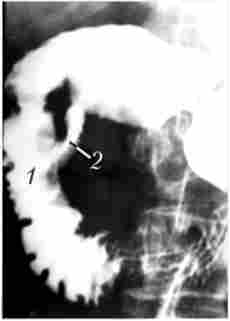

рентгенологічні дослідження. Рентгенологічне контрастне дослідження дванадцятипалої кишки дозволяє виявити патологічний процес, що розташовується не тільки в самій кишці, але і в органах, безпосередньо прилеглих до неї. Застосування релаксационной дуоде- монографій дозволяє, як правило, виявити пухлину БДС і, в деяких випадках, за непрямими ознаками - головки підшлункової залози, а також судити про стан стінок самої дванадцятипалої кишки (рис. 21.8 і 21.9). Деформація контурів, звуження просвіту ДПК, розгорнення її петлі служать непрямими ознаками, що дозволяє висловити припущення про наявність патологічних змін в ПЖ тільки в тому випадку, якщо пухлина досягне значної величини. При РПЖ відхилення від норми виявляють лише у 50% хворих.

Для з'ясування причини механічної жовтяниці і визначення рівня обтурації жовчних проток використовуються методи їх прямого контрастування '. чрескожная чреснеченочная холангиография, черезшкірна холецістохолангіографія йод контролем лапароскопа або УЗД. Завдяки високій якості одержуваного рентгенівського зображення пряма холангиография відповідає всім вимогам сучасної діагностики, дозволяючи ще до операції виявити і уточнити локалізацію обтурирующем пухлини і стан жовчних проток. При дистальної обтурації загальної жовчної протоки відзначається розширення всієї біліарної системи. Контрастне речовина не надходить в дванадцятипалу кишку, конфігурація дистального відділу жовчної протоки має вигляд конічного звуження з нерівними зубчастими або фестончастими контурами, нагадуючи кінець сигари або письмової пера (рис. 21.10).

Дуоденографія в умовах гіпотонії

Мал. 21.8. Дуоденографія в умовах гіпотонії:

1 - ділянку відсутності рельєфу слизової оболонки протягом 2 см по медіального контуру дванадцятипалої кишки у верхній половині спадної частини кишки; 2 - порожнину розпалася пухлини за межами кишки,

в яку затікає контраст

черезшкірна гепатохолангіограмма

Мал. 21.10. Черезшкірна гепатохолангіограмма.

Рак головки підшлункової залози:

При раку головки ПЖ, перехідному на панкреатичну частина жовчної протоки, рентгенологічна тінь останнього обривається в дистальному відділі у вигляді нерівній горизонтальній, напівкруглої або конічної лінії. Якщо пухлина головки ПЖ поширюється на вище розташовані відділи жовчної протоки, то тінь контрастувало жовчної протоки стає коротшим, а при залученні в процес пузирногопротоки жовчний міхур не контрастіруете ^.